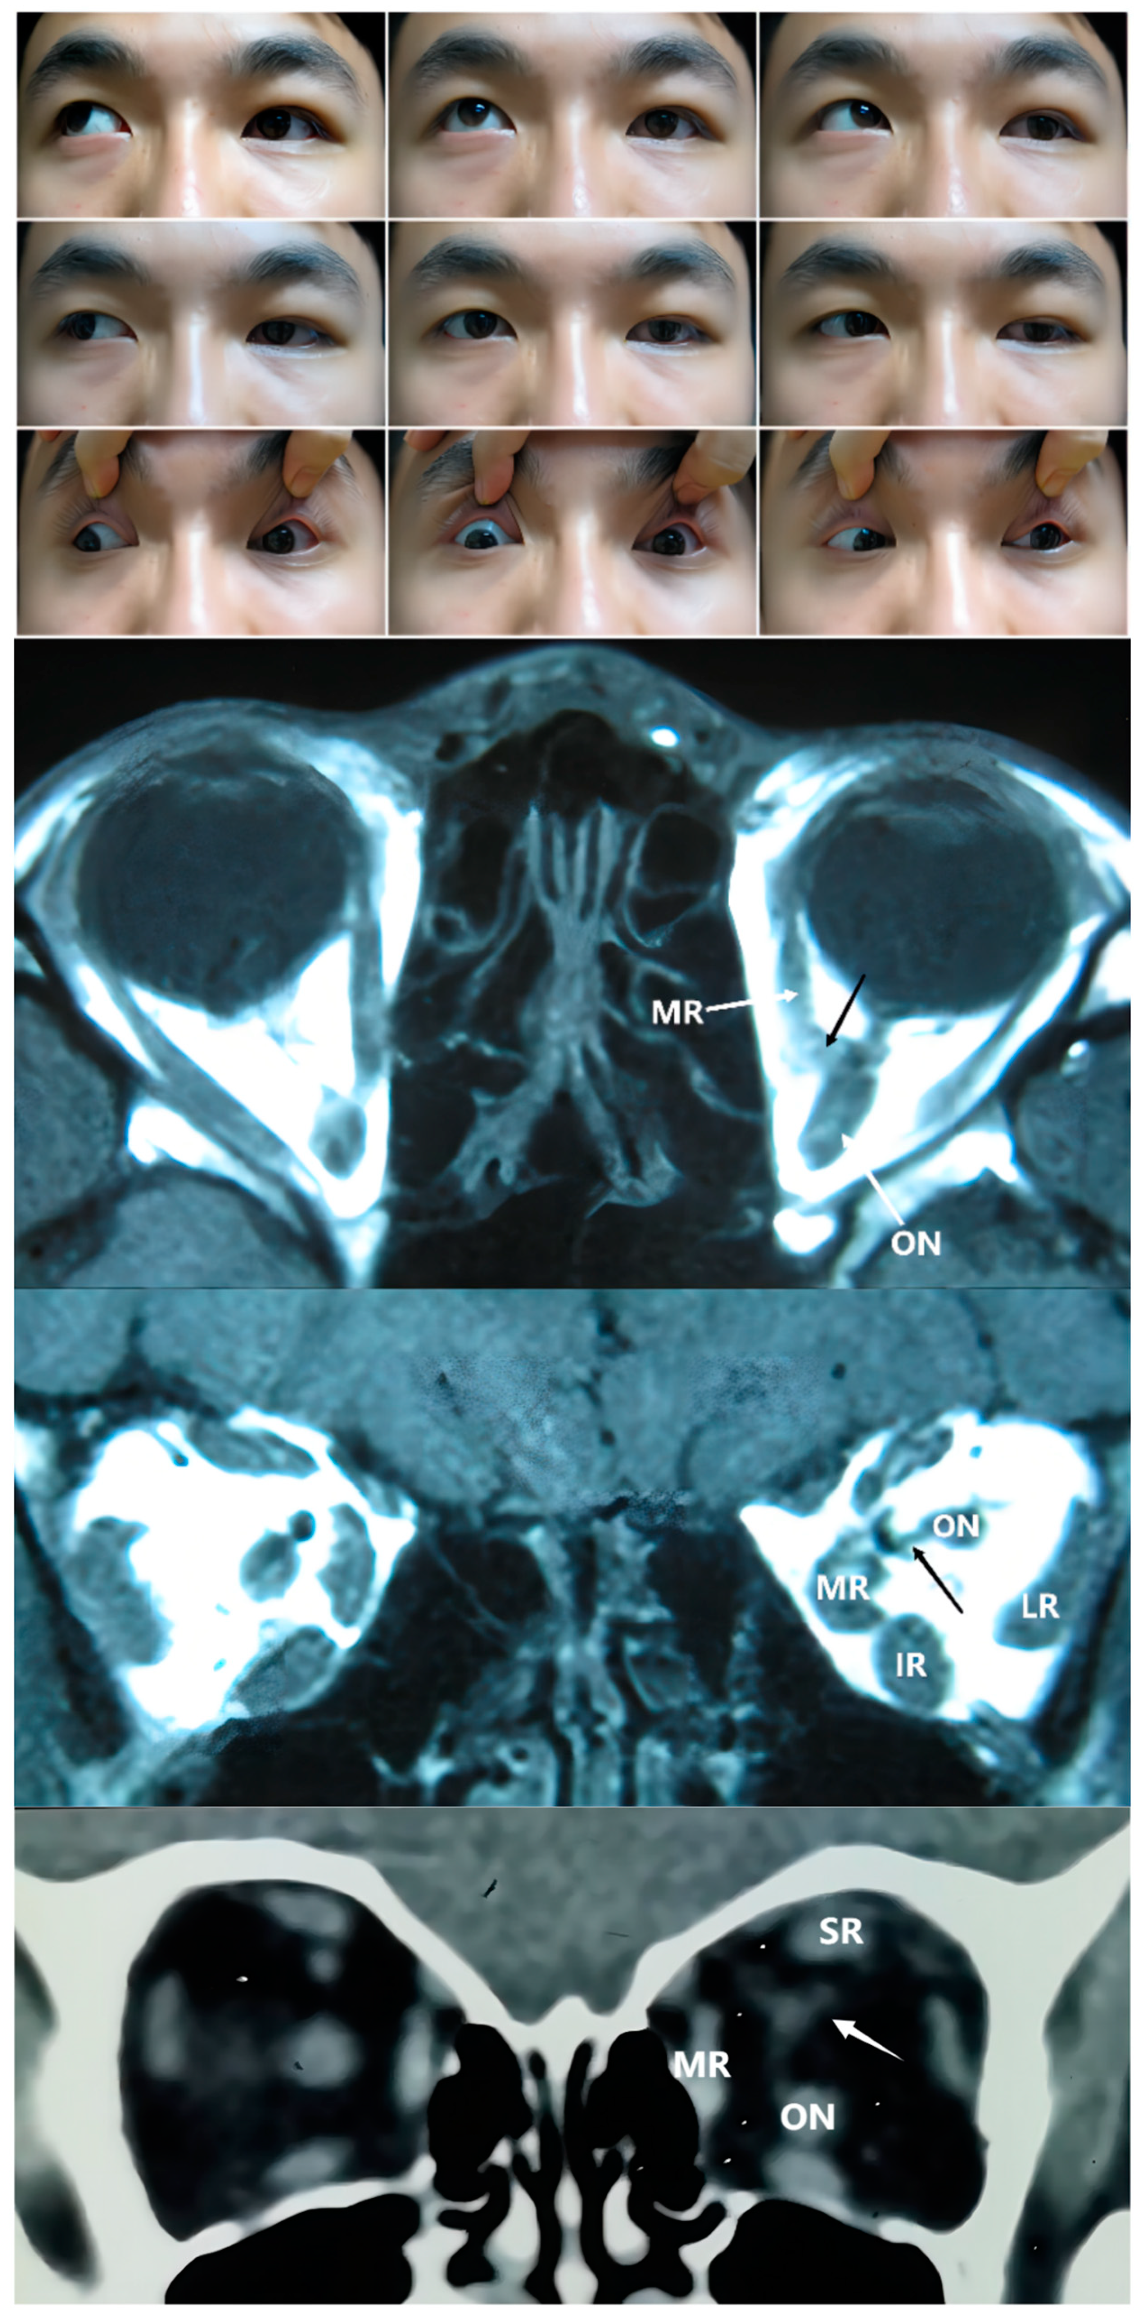

Figure 4. Upper Panel: Nine gaze photograph of Case 11 showing a 13 PD exotropia and 13 PD left hypotropia. Ocular motility determinations revealed differences in the extent of limitations in all directions. Second Panel: T1 coronal MRI of Case 11 demonstrating a muscular band between the medial rectus (MR) and optic nerve (ON) in the left orbit. Third Panel: T1 axial MRI of Case 11 showing connections. Bottom Panel: coronal CT of Case 12 showing a muscular band between the superior rectus (SR) and optic nerve in the left orbit. IR: inferior rectus; LR: lateral rectus.

The fourth classification type, with connections between recti muscles and the ON, has rarely been reported. No anomalous connections were observed between recti. Tetsu Naito et al. found that part of the structure of the SR and LR coursed from the sheath of the optic nerve or the oculomotor nerve [21]. The changes occurring during the short period of fetal development may remain rather than degenerate in the patients with additional tissue between the rectus and the optic nerve. In type 2 and type 3 cases, the optic nerve can also be surrounded by anomalous tissue (as in Case 2 in Figure 2), which may be associated with hypoplastic optic nerves. Cases 11 and 12 experienced amblyopia in the affected eye, with a mild fundus hypoplasia observed under ophthalmoscopic examination in Case 12.